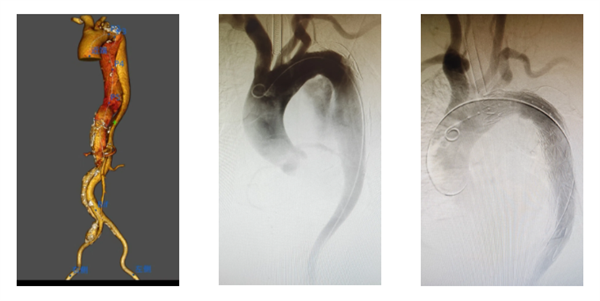

患者为老年女性,夹层动脉瘤瘤体直径达6.8cm,第一破口紧邻左侧锁骨下动脉,夹层一直累及右侧髂动脉,同时,患者合并房颤、高血压等基础疾病。传统手术创伤大、风险高。面对挑战,安医二附院血管外科专家团队与我院多学科紧密协作,经充分术前讨论,最终确定采用TEVAR联合预置缝合器技术。手术全程仅耗时20分钟,无切口,术后患者生命体征平稳,术后首日即可自主下地活动,目前已进入康复阶段,患者及家属对治疗效果十分满意。